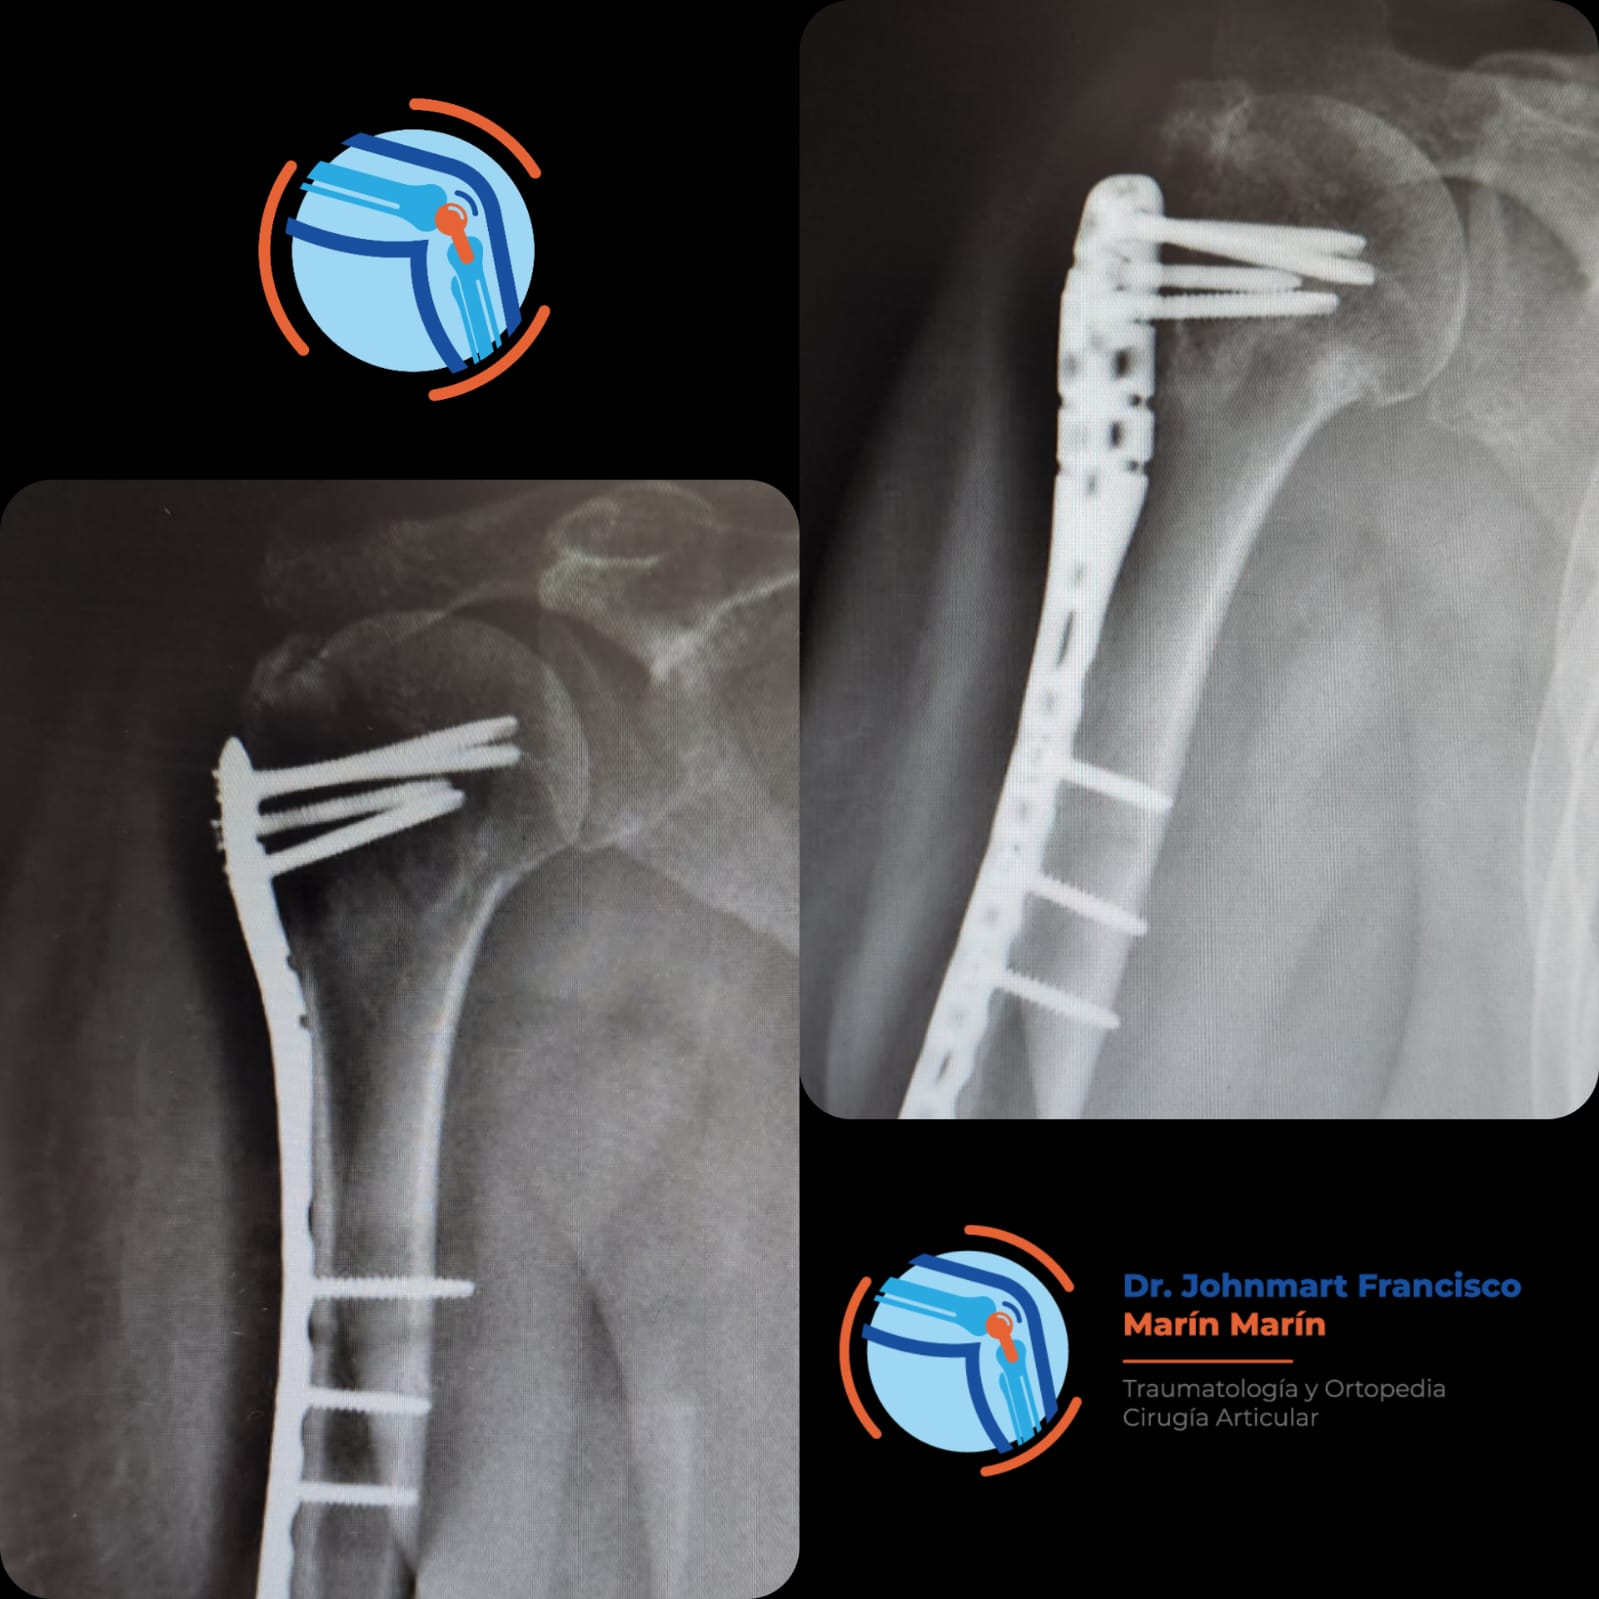

Atención a Lesiones

Lesiones Deportivas

Lesiones graves como fracturas, rupturas de ligamentos, esguinces o incluso luxaciones.